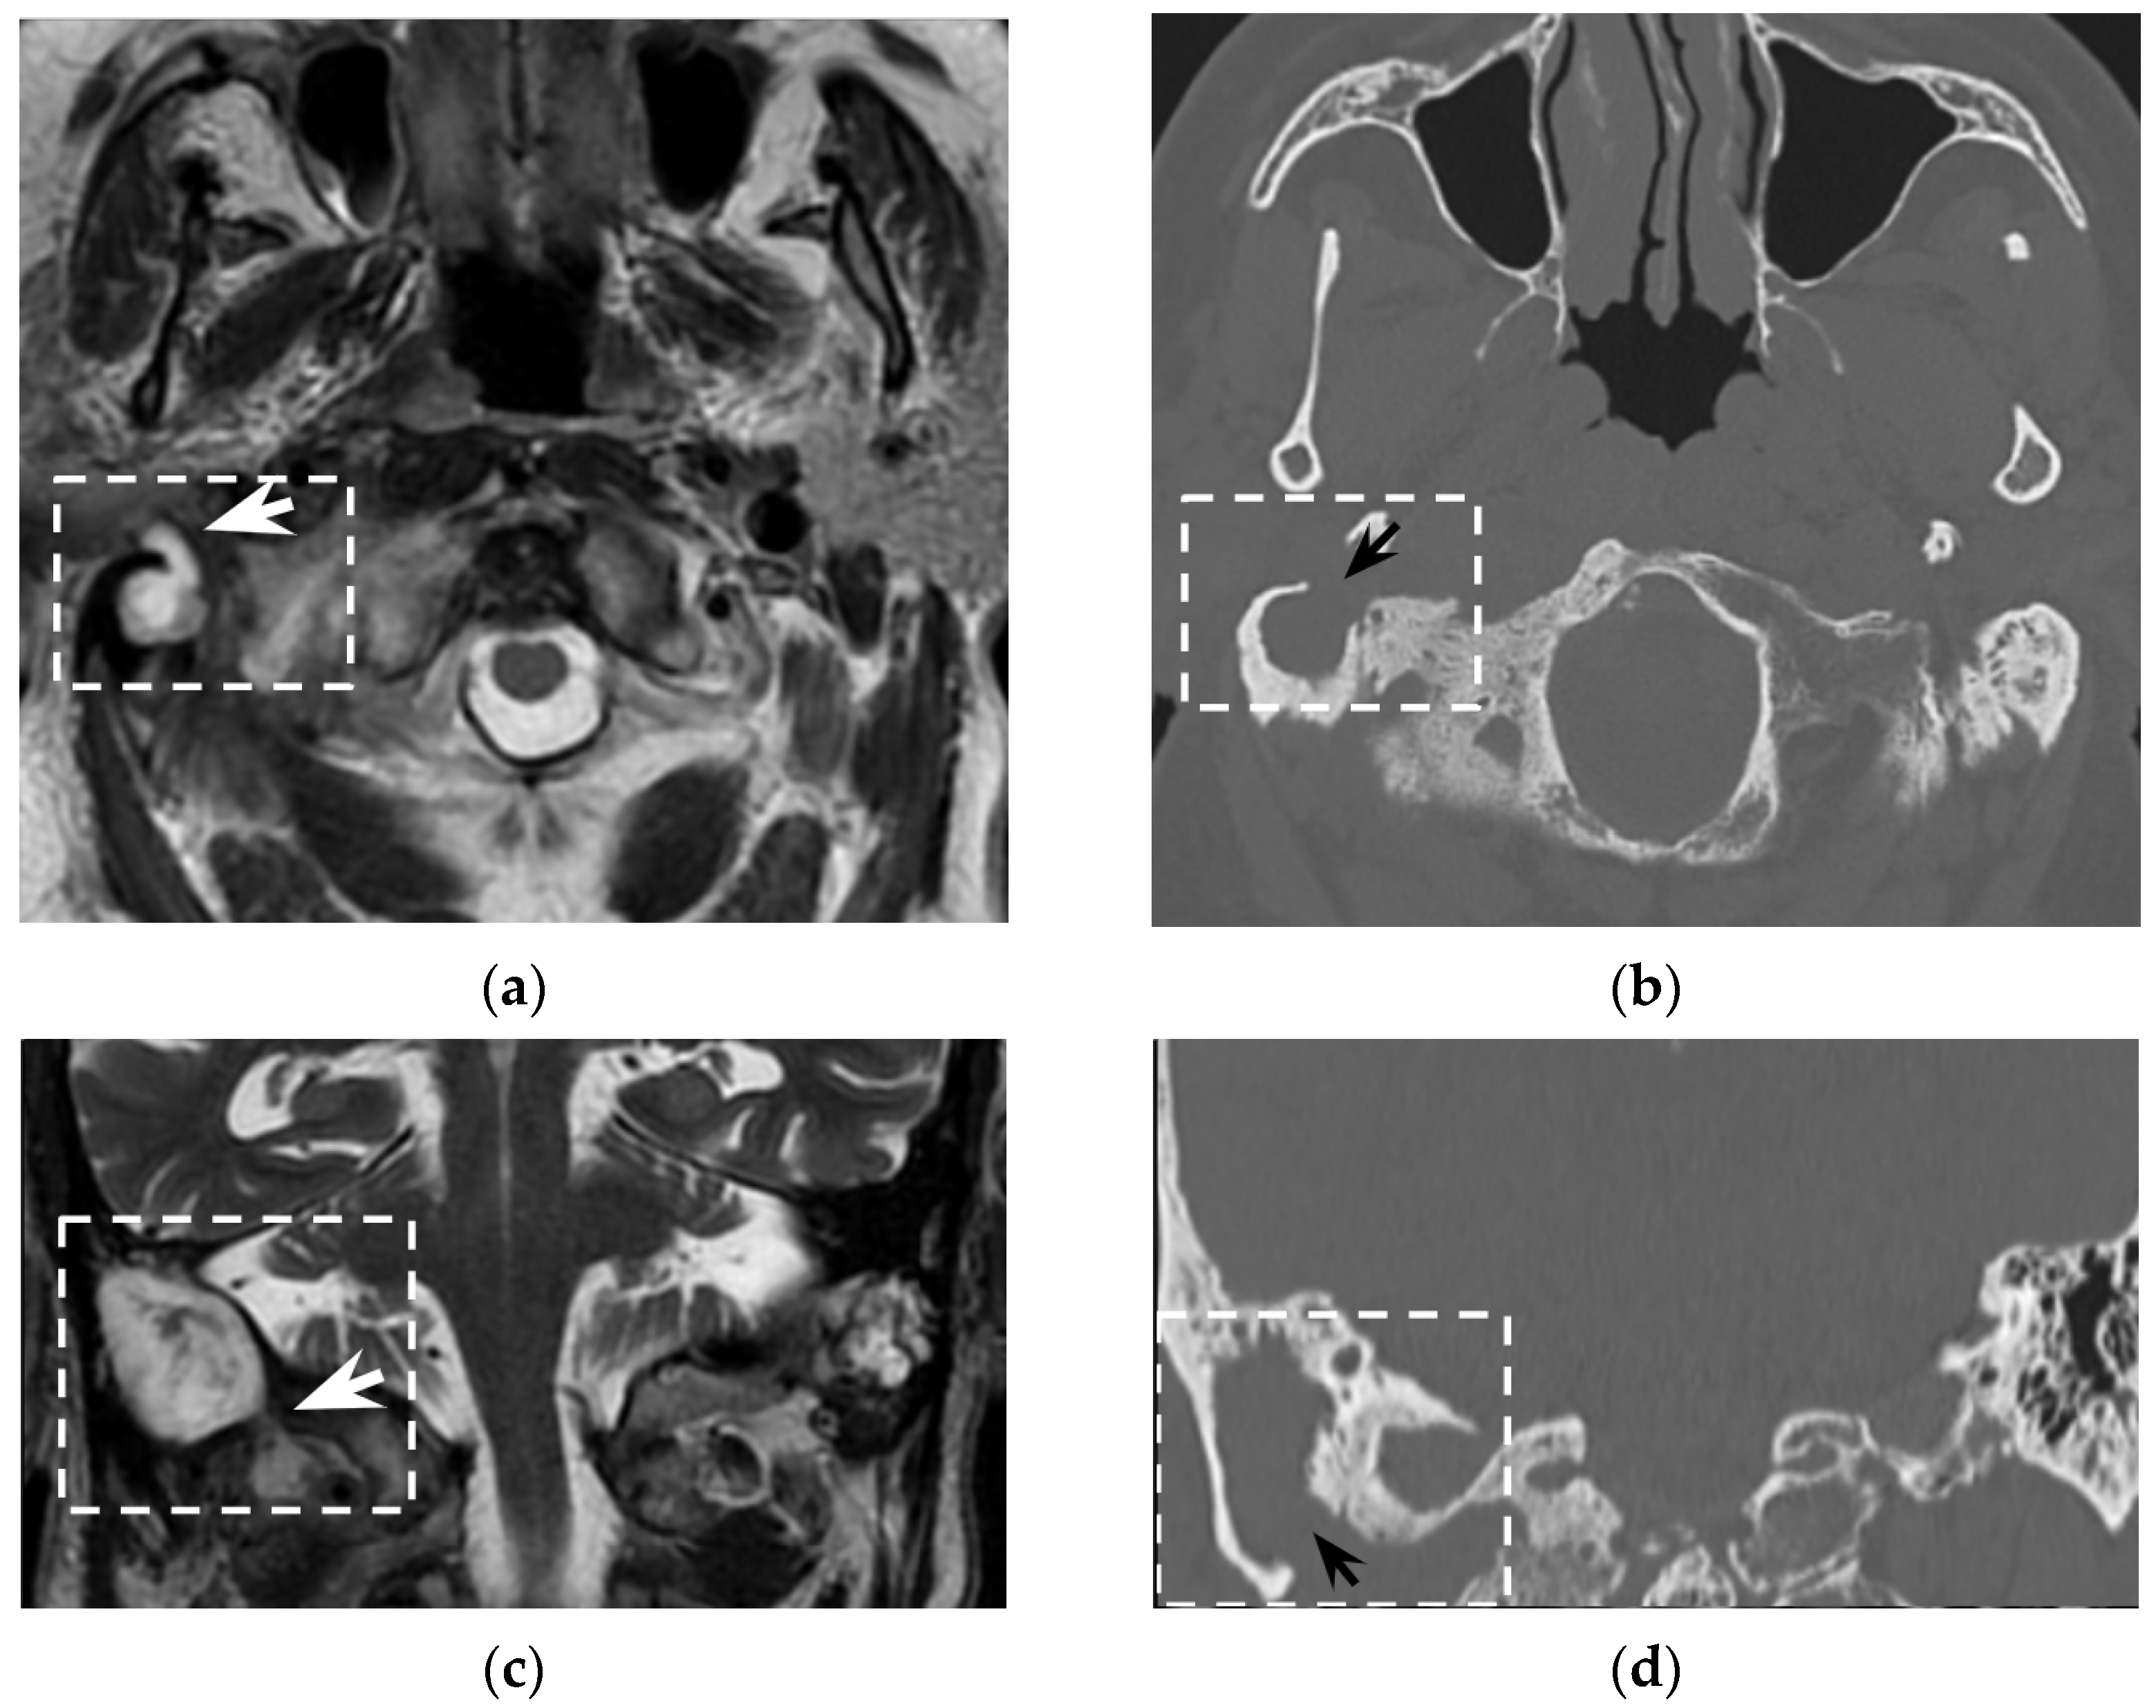

Figure 6. Thirty-seven-year-old man with chronic otitis media and history of ear surgery. MRI T1w (a) and contrast-enhanced T1w (b) sequences showing hypo-isointense material in the left mastoid (black arrows) spreading in the neck, in the posterior cervical space (white arrowheads). Note the mastoid mucosal enhancement, suggestive for mastoiditis, and the peripheral enhancement of the neck component (b). The material in the mastoid is hyperintense in diffusion-weighted imaging (c) and shows inhomogeneous apparent diffusion coefficient values (d), consistent with purulent collection and cholesteatoma. Bezold’s abscess and left mastoid cholesteatoma were confirmed at surgery.